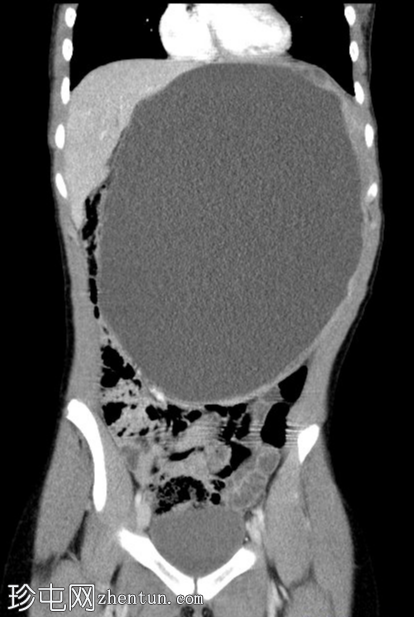

轴位增强扫描(门静脉期)

脾脏内可见巨大、边界清晰的囊肿,囊肿内有多个较小的囊肿。脾脏被拉伸并覆盖于囊肿之上,形成“爪状征”。囊肿大小为26 cm x 20 cm x 16 cm。囊肿内有单分隔,下壁可见多处钙化。

无实性成分。无子囊肿。囊肿将胃向上推移,将肝脏向右推移,并将肠道推向盆腔。腹主动脉旁可见亚厘米级淋巴结。其他实质性器官均正常。无腹水。骨骼结构正常。

为进一步明确腹部肿块的性质,医生安排了腹部CT检查¹。结果显示,脾脏起源处有一个边界清晰的巨大囊肿,囊肿内包含多个较小的囊肿。该囊肿大小为26 cm x 20 cm x 16 cm。

囊肿下部可见单隔膜和多发钙化灶。无实性成分。无子囊肿。囊肿将胃向上推移,将肝脏向右推移,并将肠道推向盆腔。主动脉旁可见亚厘米级淋巴结。其他所有实质性器官均正常。无腹水。骨骼结构正常。